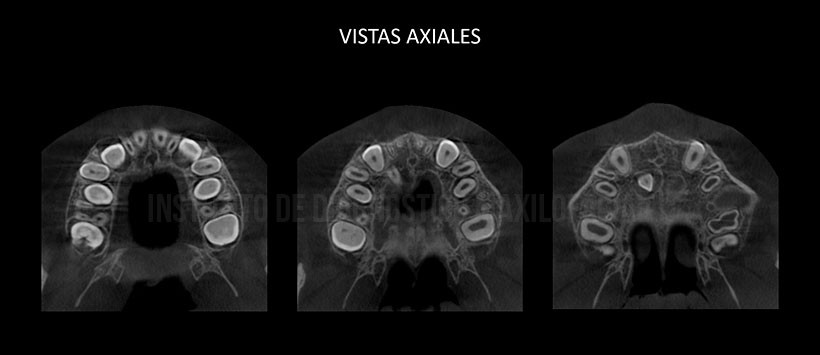

A la evaluación de la tomografía volumétricas de haz cónico se evidencio la presencia de una pieza supernumeraria localizada en el paladar duro y en posición vertical, próxima a las piezas 13 y 12. Así mismo el segmento coronario se encuentra orientado hacia el piso de fosa nasal de lado derecho, presentando un aumento de saco pericorornario. (Figura 2 y Figura 3)